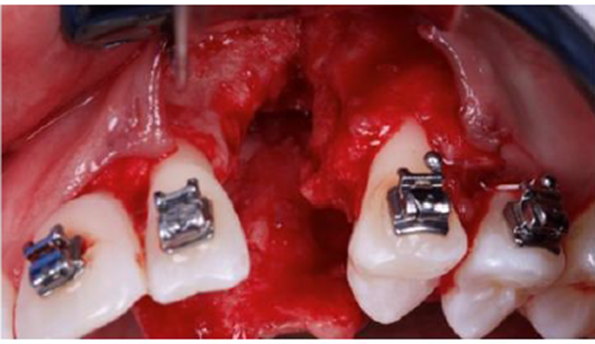

Antes da instalação do implante, tornou-se necessário um aumento vertical cirúrgico para que o implante pudesse ser colocado em uma posição tridimensional correta (Figura 2).

A incisão do envelope muco periosteal foi realizada com um bisturi número 15C, desde o incisivo central direito até o primeiro pré-molar esquerdo. Após o descolamento da mucosa vestibular, também foi descolado a mucosa palatina (Figura 3).